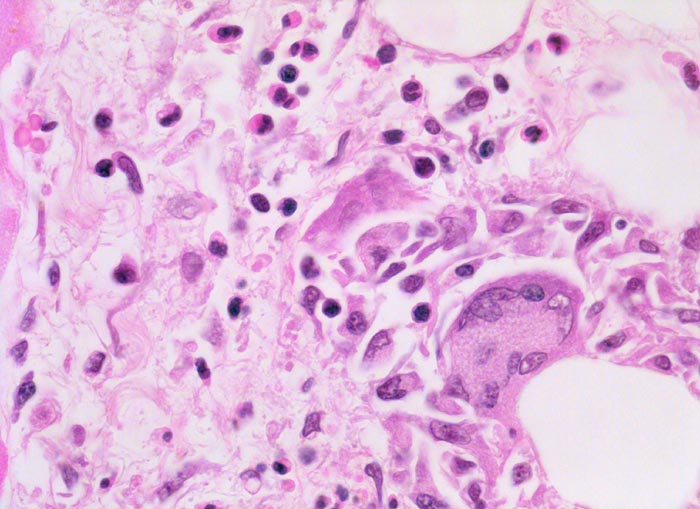

Man unterscheidet infektiöse und nicht infektiöse Ursachen. Am häufigsten ist die Assoziation mit einem viralen Infekt (primär kardiotrope Enteroviren vor allem Coxsackievirus B oder nicht kardiotrope Viren im Rahmen einer allgemeinen Virusinfektion). Bakterien, Pilze, Protozoen, Helminthen, Chemikalien, Umweltgifte (Blei, Arsen, Kohlenmonoxid), Bestrahlung und verschiedene Systemerkrankungen (SLE, Riesenzellarteriitis) können ebenfalls eine Myokarditis verursachen. Die Hypersensitivitätsmyokarditis wird in Zusammenhang mit einer Überempfindlichkeitsreaktion auf verschiedene Medikamente beobachtet (Penicillin, Ampicillin, Hydrochlorothiazid, Methyldopa, Sulfonamide…). Typisch ist ein gemischtes Entzündungsinfiltrat aus Lymphozyten, Plasmazellen, Makrophagen und auffallend vielen eosinophilen Granulozyten. Zahlreiche Medikamente verüben wahrscheinlich einen direkten dosisabhängigen toxischen Effekt auf das Myokard (Lithium, Doxorubicin, Kokain, Catecholamine, Acetaminophen, Anthrazyklin, Zidovudin…). Die Riesenzellmyokarditis ist eine seltene idiopathische Erkrankung, charakterisiert durch eine massive Destruktion der Herzmuskelzellen durch mehrkernige Riesenzellen in Begleitung von Lymphozyten, Plasmazellen und eosinophilen Granulozyten (> 9757) (> 9756). Weitere nicht infektiöse Formen der Myokarditis sind die hypereosinophile Myokarditis, die rheumatische Myokarditis im Rahmen eines rheumatischen Fiebers und die granulomatöse Myokarditis bei Sarkoidose (> 10020).

• Teils fleckförmiges, teils diffuses gemischtes Entzündungsinfiltrat aus Lymphozyten, Plasmazellen, Makrophagen und zahlreichen eosinophilen Granulozyten.

• Einzelne Herzmuskelzellen werden durch das Entzündungsinfiltrat zerstört und sind hypereosinophil (Myozytolyse).